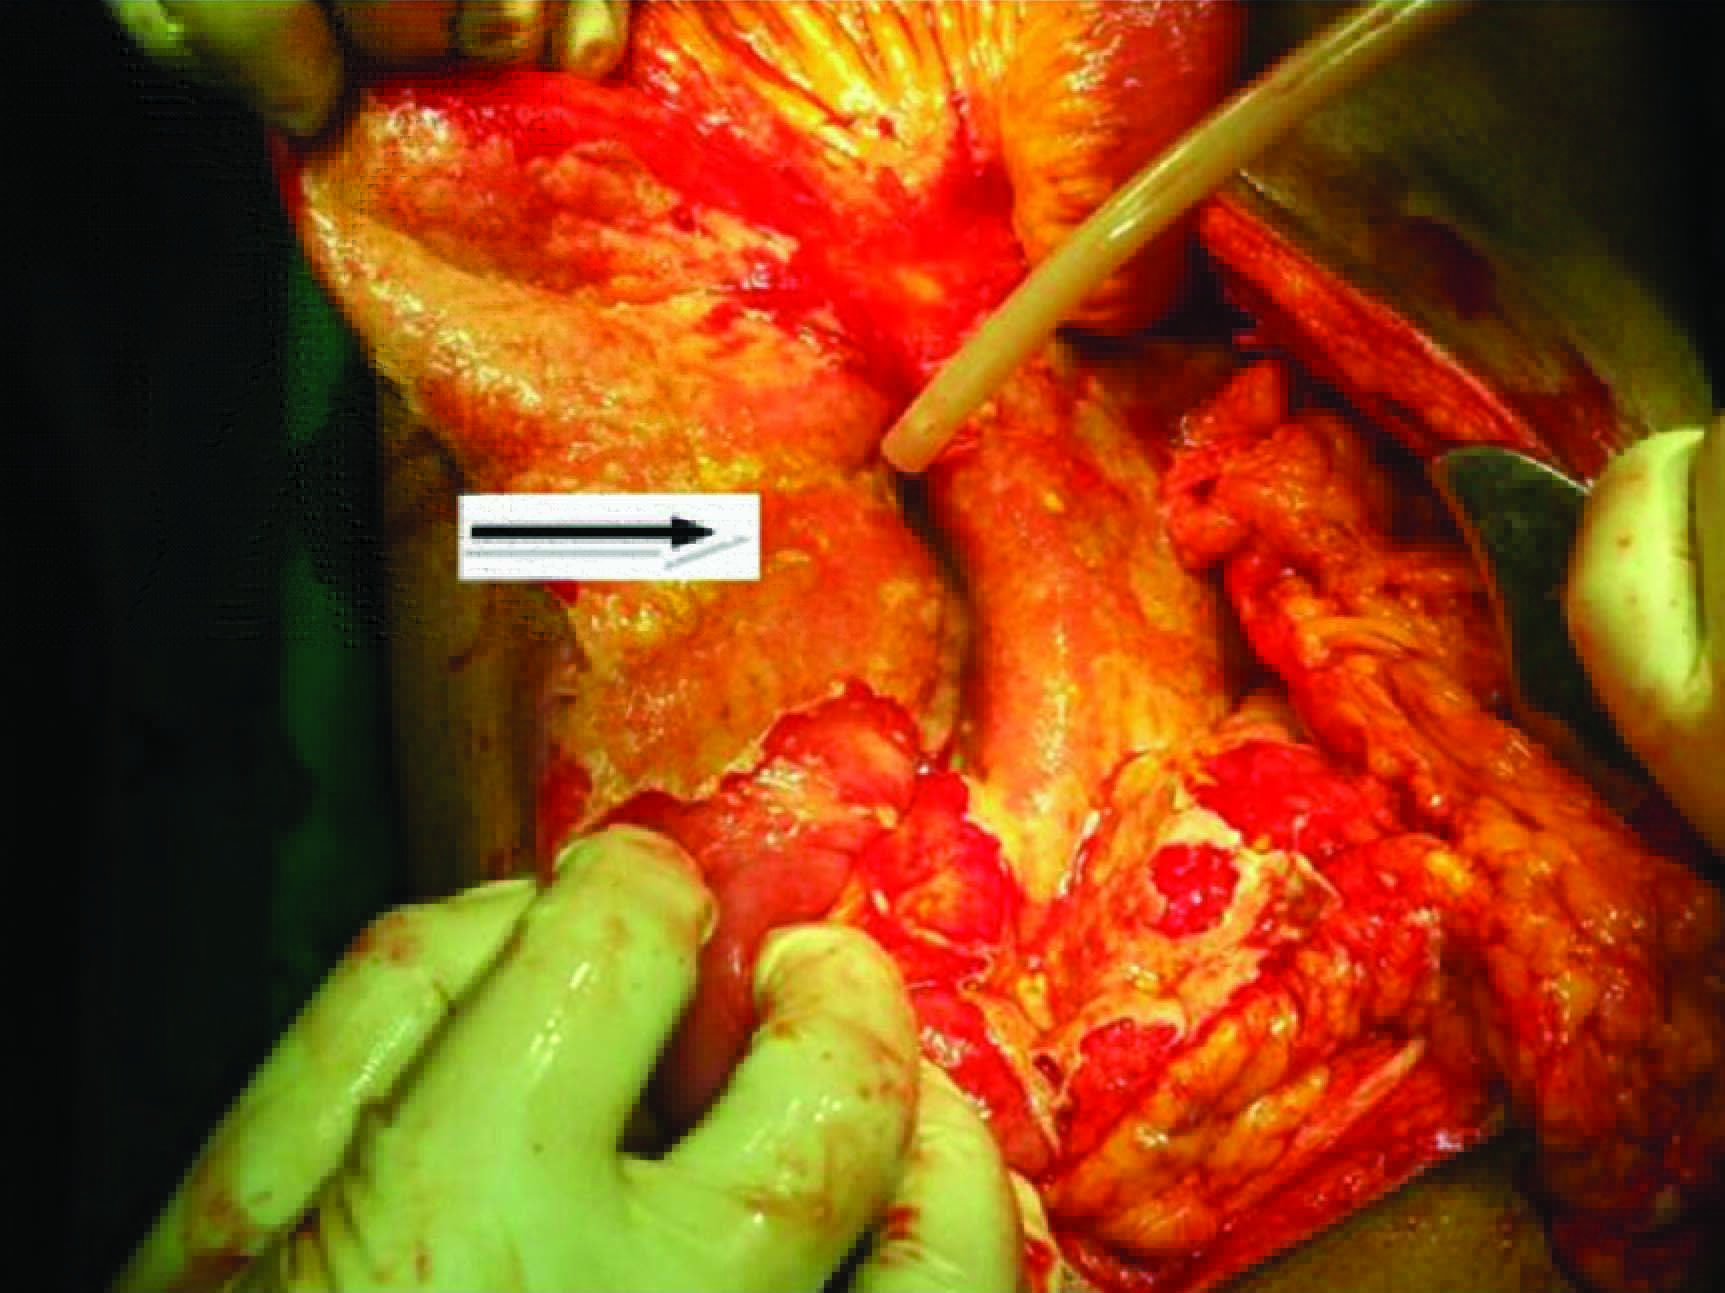

A midline laparotomy incision was taken. Around 1500 ml of free fluid in the abdomen was suctioned. A mass was noted in Rt hypochondriac region extending to umbilical region with omentum covering it. As soon as the omentum was released around 500ml of bile stained thick pus which was contained in the mass by coils of small intestine, ascending and transverse colon, and omentum, seeped out [Table/Fig-1]. The same was drained and the stomach, small and large intestine were examined. A jejunal perforation was present around 15 cm distal to duodenojejunal flexure and an annular constricting stricture was noted 2 cm distal to the perforation [Table/Fig-2]. The jejunum distal to the stricture was dilated upto 10 cm [Table/Fig-3]. Segmental resection of unhealthy jejunum of about 20 cms long with two layered end to end anastomosis was done (enteroenterostomy) [Table/Fig-4]. Mesenteric lymph node sampling was done. Histopathological examination of the jejunal specimen and mesenteric lymph nodes showed no evidence of tuberculosis and an impression of non specific ulcer with perforation and fibrous stricture was given [Table/Fig-5]. Patient, now after six months, is doing well and is under regular follow-up.

The perforated jejunal loop along with the bile stained pus was contained by omentum and bowel loops in this mass. Note thick flakes coating the bowels,